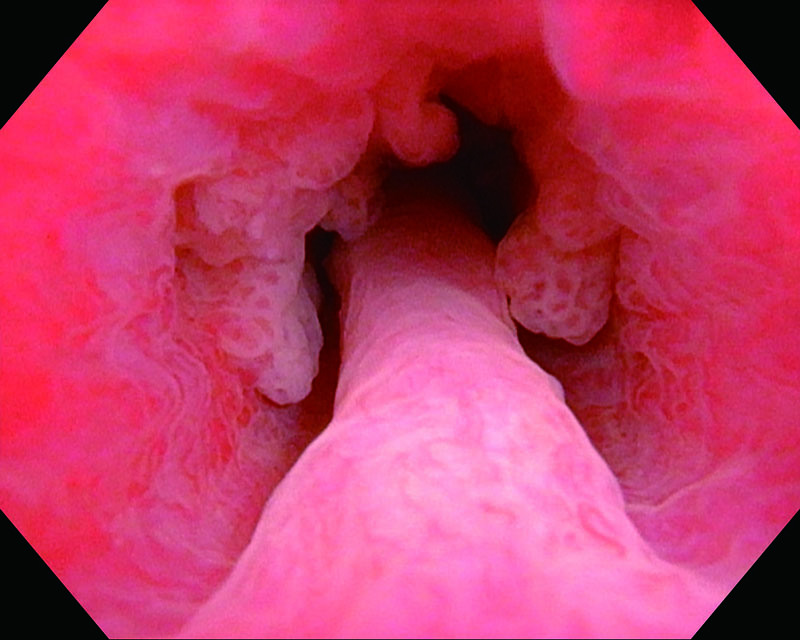

乳頭型・広基性 87歳・男性

通常光

NBI

病理 UC, High grade(G3)

コメント

浸潤性膀胱癌の前立腺部尿道への進展。悪性度の高い乳頭型腫瘍、結節型腫瘍。